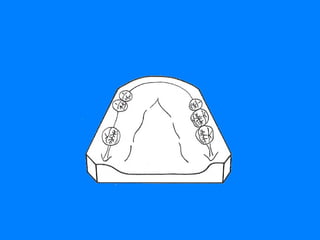

CLASE I AREAS EDENTULAS BILATERALES UBICADAS POSTERIORMENTE A LOS DIENTES  NATURALES REMANENTES SITUACION DE EDENTICION PARCIAL QUE CON MAS FRECUENCIA SE PRESENTA

CLASE I DE KENNEDY  RESTAURACION DENTO MUCO-SOPORTADA LIMITACION 15 – 26 PRESENCIA DE MAYOR NUMERO DE DIENTES PILARES. REDUCE LA EXTENSION DE LOS REBORDES RESIDUALES

CLASE I DE KENNEDY RESTAURACION DENTO-MUCOSOPORTADA LIMITACION 36-44 La disminución del soporte mucoso, hace que los dientes pilares asuman un papel protagónico en las funciones de S.E.R.